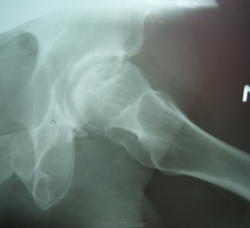

Пол пациента: Мужской пол Тип патологии: Врожденная патология Область исследования: Скелетно-мышечная система Методы исследования: Rg Мужчина 40 лет после падения с 3 этажа почувствовал болезненность в т\б суставах. Травма произошла около3 месяцев назад. Был сделан снимок. https://radiomed.ru/sites/default/files/styles/case_slider_image/public/user/712/sl273619.jpg?itok=ZJ42angR https://radiomed.ru/sites/default/files/styles/case_slider_image/public/user/712/sl273620.jpg?itok=_YJo-xg7 ID:13714 Wed, 27/04/2011 - 19:45 #1 Игорь Иванович Offline Last seen: 3 years 11 months ago Joined: 23.01.2010 - 14:56 Posts: 3695 Асептический некроз головки бедренной кости, стадию подскажут академики сайта. Thu, 28/04/2011 - 06:48 #2 Kuzmitch Offline Last seen: 12 years 8 months ago Joined: 01.10.2010 - 18:20 Posts: 171 Позволю себе предложить стадию импрессионного перелома переходящую в стадию секвестрации, выраженного артроза нет Thu, 28/04/2011 - 15:16 #3 lupan Offline Last seen: 6 years 11 months ago Joined: 07.01.2010 - 17:17 Posts: 1406 Игорь Иванович wrote: Асептический некроз головки бедренной кости, стадию подскажут академики сайта. Обоих костей. Великое преймущество врача заключается в том, что он не обязан следовать собственным советам. ( А. Кристи)

Асептический некроз головки бедренной кости, стадию подскажут академики сайта.

Позволю себе предложить стадию импрессионного перелома переходящую в стадию секвестрации, выраженного артроза нет

Обоих костей.